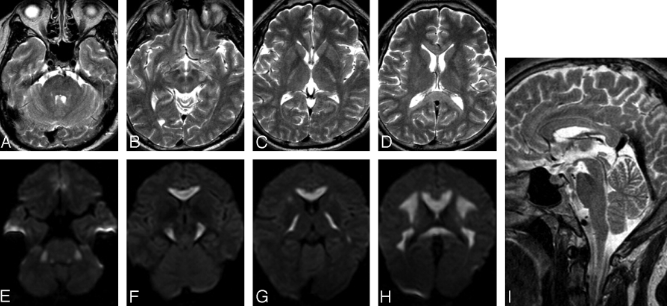

31岁,男性,长期饮酒,出现急性失语、短期注意力和记忆力缺陷,胼胝体及半卵圆中心对称性异常信号,扩散受限,未见强化,经过维生素B1/6/9/12治疗后病灶吸收明显,诊断为原发性胼胝体变性急性期。

48岁,男性,长期饮酒过量20年,出现出现眩晕,胼胝体、侧脑室周围白质、内囊后肢对称性异常信号,扩散受限,诊断为原发性胼胝体变性急性期。